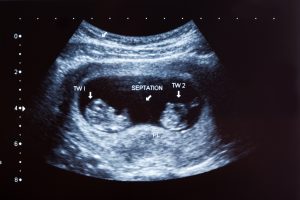

EPAU is a specialist unit that provides care for women with problems in early pregnancy. This often centres around the provision of an ultrasound scan to confirm the location and viability of pregnancy. In EPAU, patients are referred from the community midwife (CMW), GP, A&E, urgent care or follow ups of EPAU. The most common reasons women are referred are bleeding and/or pain with a positive pregnancy test. Women may also be referred based on their previous problems in early pregnancy, such as ectopic pregnancy, molar pregnancy or multiple miscarriages, so that they can be assessed early in the subsequent pregnancy and an ultrasound scan is done.

All pregnant women up to 16 weeks are seen in this area (cut off for gestation may vary as per different hospitals).